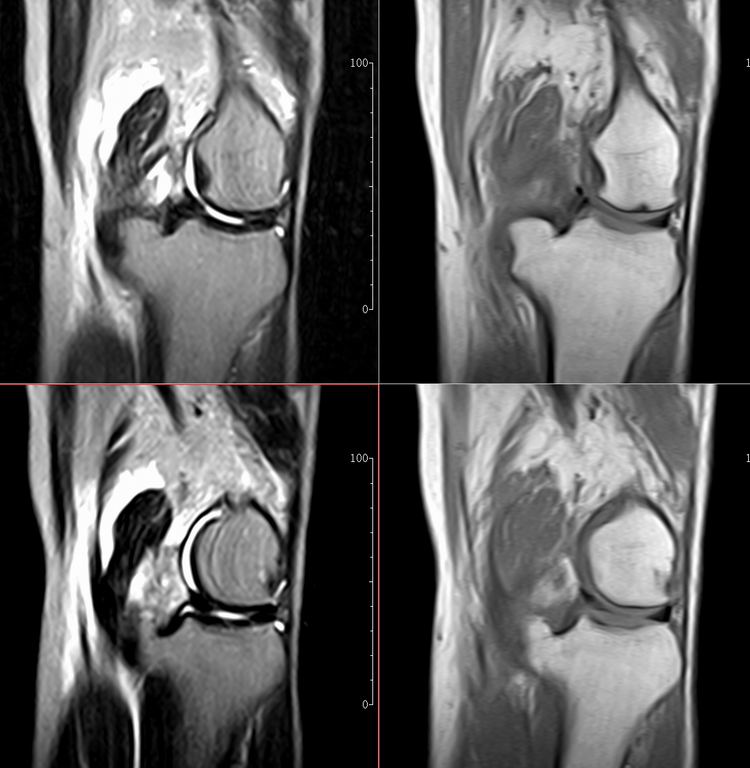

标题: MRI1910:M 687Y。近日因外伤疼痛,而就诊。

m 687y。近日因外伤疼痛,而就诊。有外侧副韧带损伤吗??因片子较差各位请包涵。

这算什么位置呢?矢状位?冠状位?

关节退行性变伴股骨外髁关节面下囊肿,不除外剥脱性骨软骨炎.关节积液,髌骨软化症

体位不标准。关节退变伴关节积液。

1)膝关节骨质退行性改变。

2)由于体位的关系不能确定有外侧副韧带的损伤。

关节退变伴关节积液,外侧副韧带的损伤

关节积液,外侧副韧带的损伤